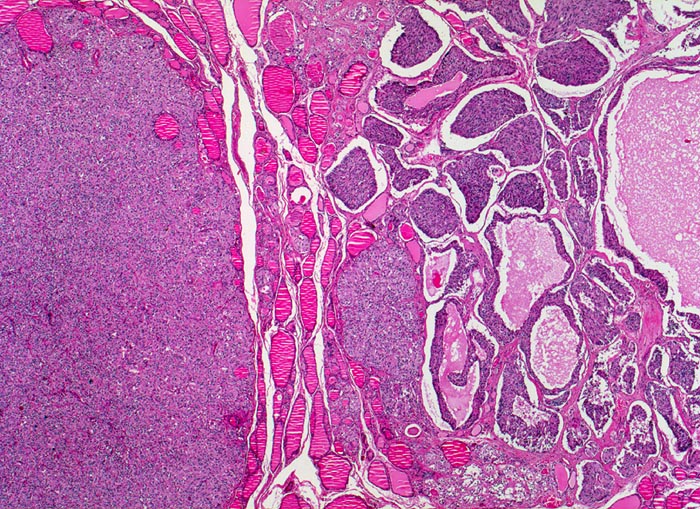

PathoPic – image database / PathoPic ID 4854 - medulläres Schilddrüsenkarzinom

medulläres Schilddrüsenkarzinom

Schilddrüse

Solide, invasiv wachsende Tumorinfiltrate mit zystischen Hohlräumen. Stellenweise finden sich Inseln von Schilddrüsenparenchym innerhalb der Tumormasse.

Mehrere scharf begrenzte weisse Knoten in beiden Schilddrüsenlappen von bis zu 8mm Durchmesser.

Beim Vater der Patientin wurde ein bilaterales Phäochromozytom diagnostiziert und in der Folge eine multiple endokrine Neoplasie vom Typ 2A. Im Familienscreening wurde bei der Patientin eine Mutation im Ret-Protoonkogen nachgewiesen und eine prophylaktische Thyreoidektomie durchgeführt.